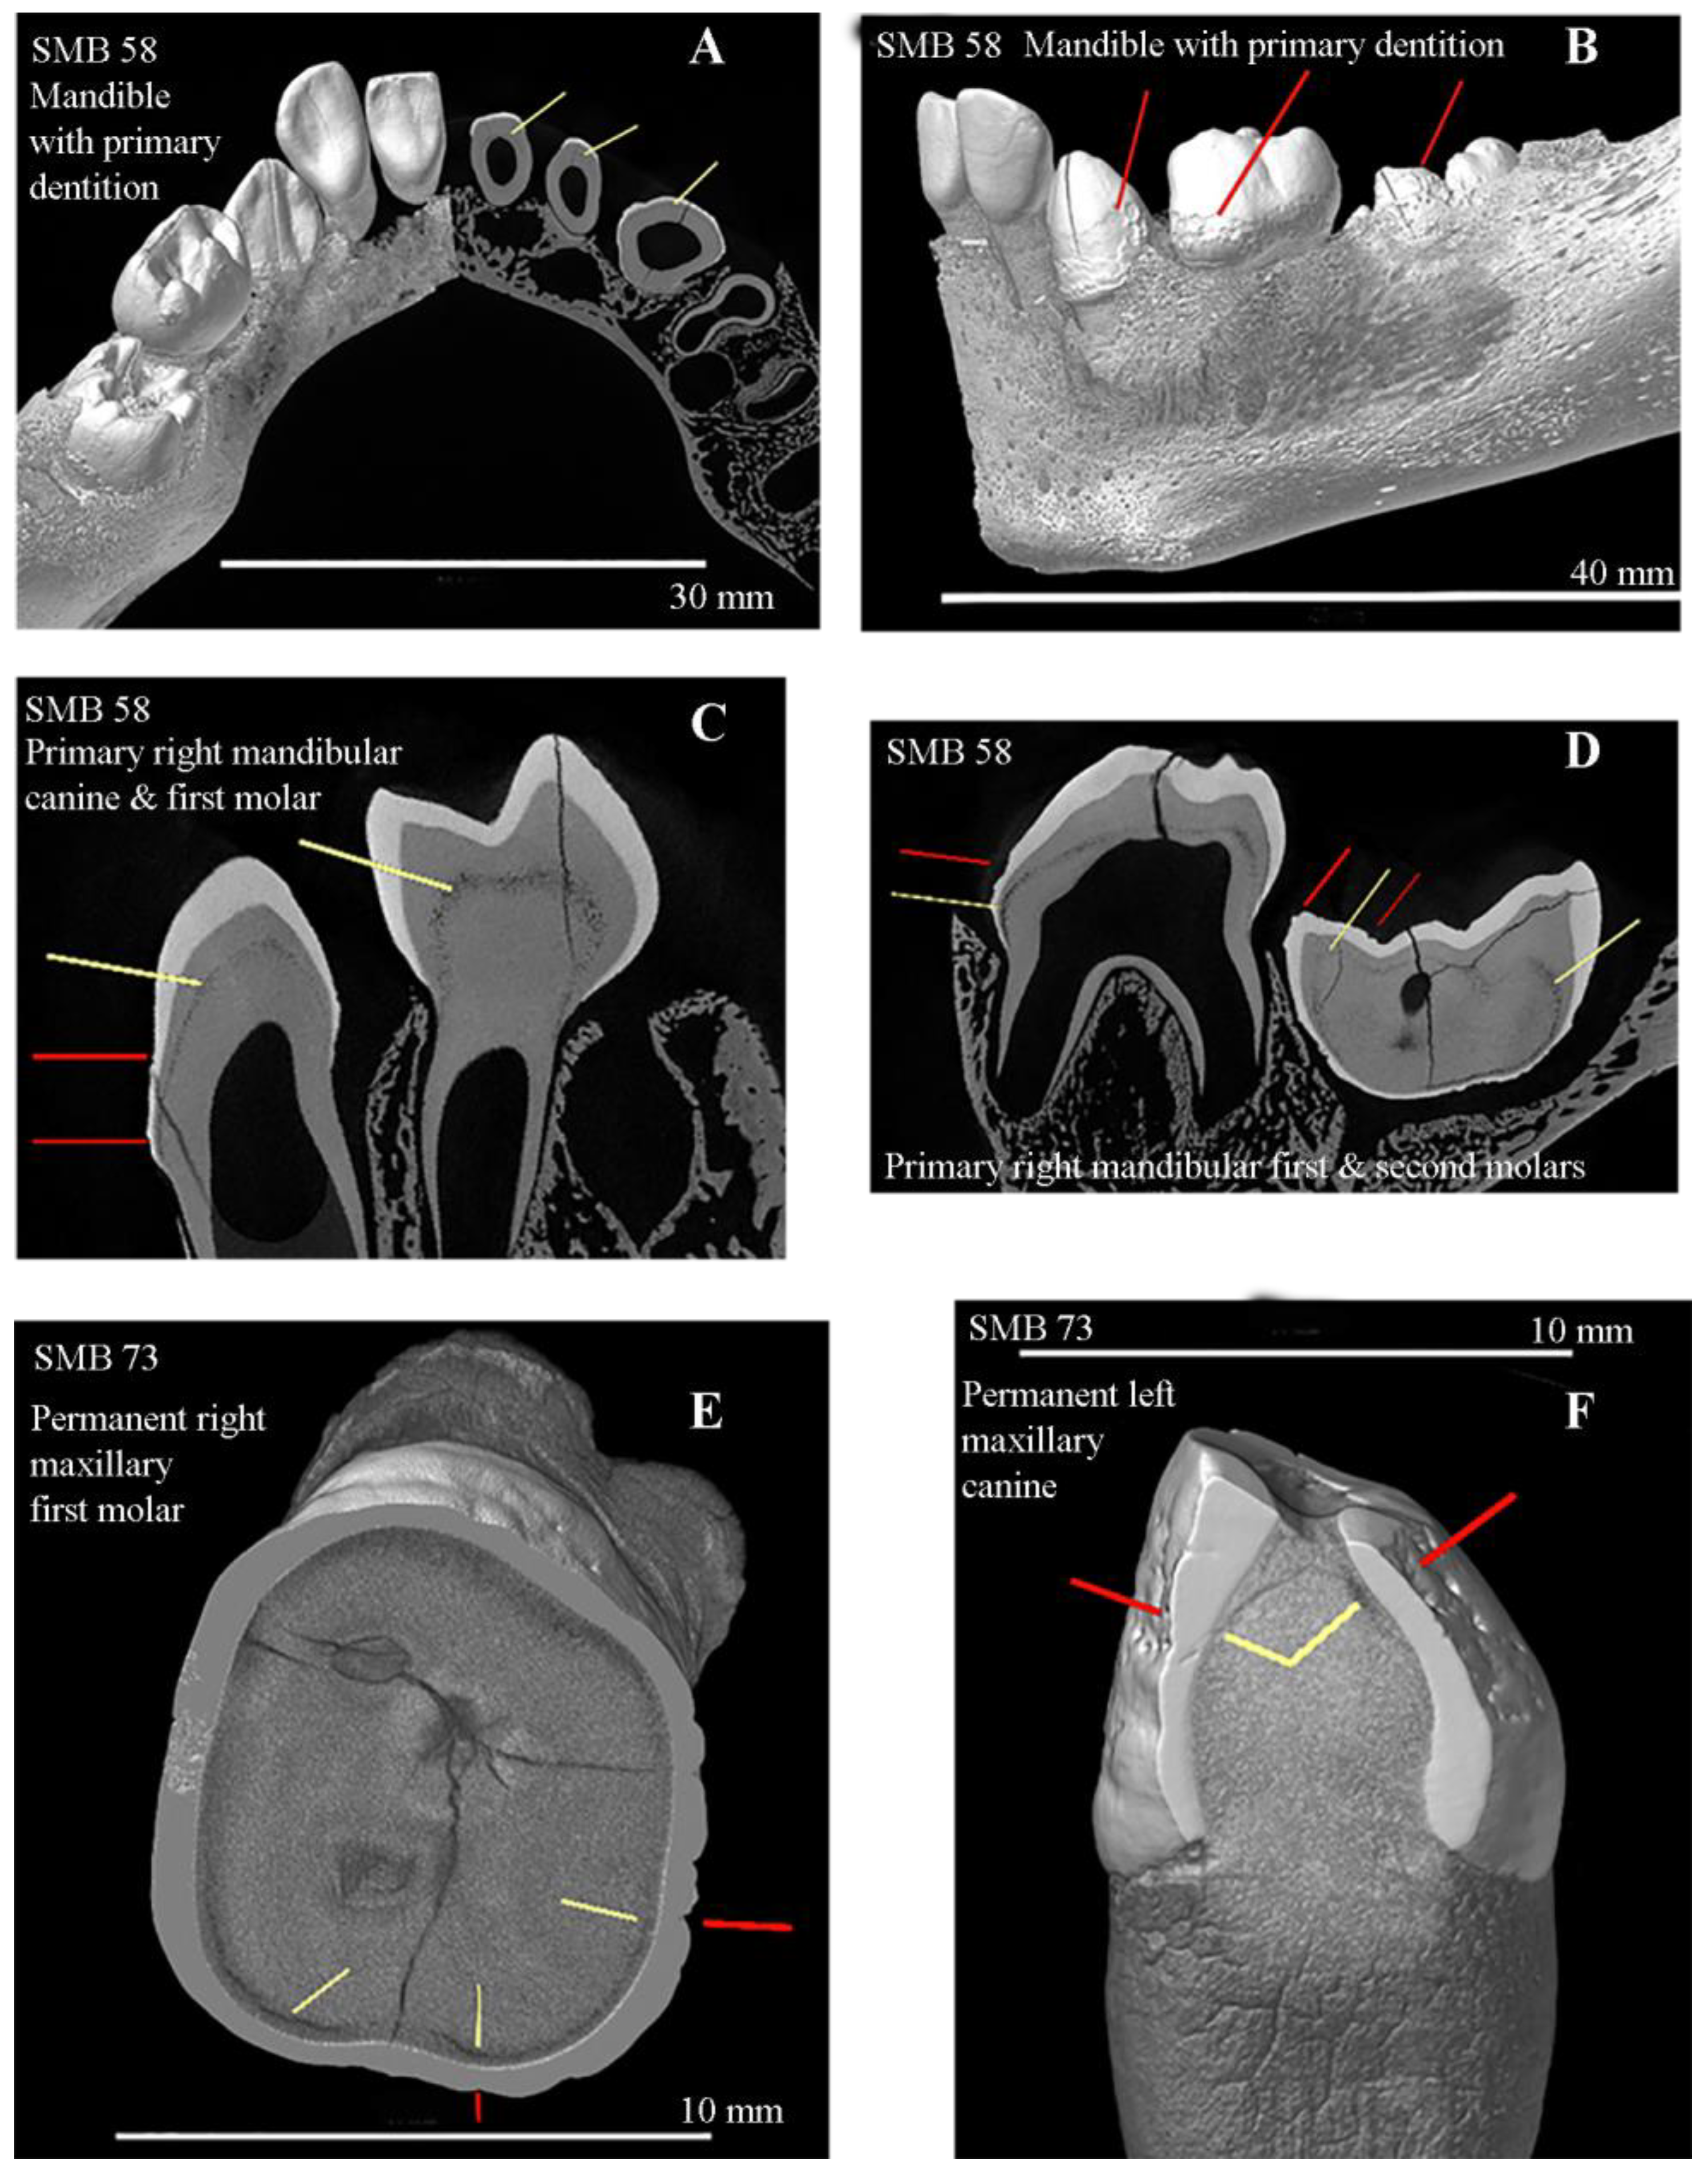

| SMB 58 | 0–2 | U | 11 | All primary teeth | 51, 52, 54, 61, 62, 72, 74, 84 | 8 | 72% | Linear and pits |

| SMB 58 | U | D= 1–1.5 (±3 months) S= 0–2 | 10 de | 0 | 1 | 0 | 9/10 | 10/10 | (i) Abnormal porosity of the cortical bones of the maxilla and mandible [1]. |

| SMB 73 | M | D = over 23.5 S = 30–39 | 19 P | 17/19 | 1–3 | 15/19 | 18/19 | 7/19 | (i) Torticollis, (iii) spina bifida occulta. |

| SMB 73 | 30–39 | M | 19 | Permanent | 11, 12, 13, 16, 21, 23, 25, 31, 32, 33, 34, 41, 42, 43, 44 | 15 | 79% | Linear and pits |